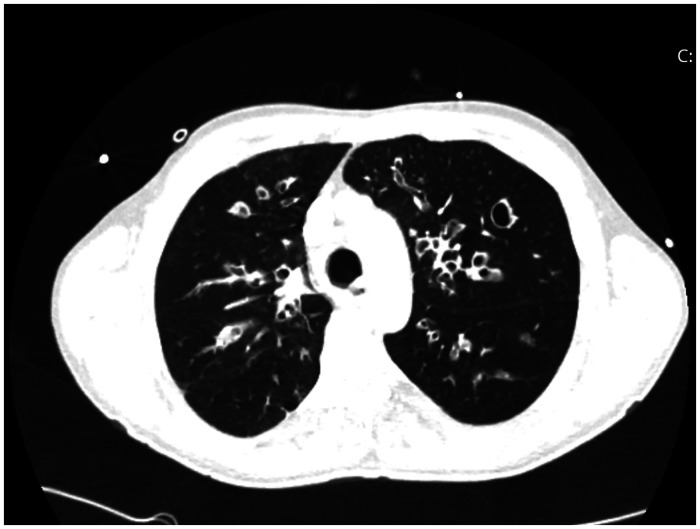

囊性纤维化患者可考虑肺移植。尽管与其他患者相比,这些患者可能经历更成功的结果和生存率,但可能出现各种并发症。特别是,感染性并发症和脓毒性死亡在囊性纤维化患者中可能比其他肺移植适应症更普遍。考虑到所有这些因素,识别和处理该患者组术后可能出现的并发症至关重要。在这篇文章中,我们按时间顺序介绍了一例因囊性纤维化而接受肺移植的患者在移植后发生的多种危及生命的并发症,并对其处理进行了讨论。

Cystic fibrosis patients may be considered for lung transplantation. Although these patients may experience more successful outcomes and survival rates compared to others, various complications can arise. In particular, infectious complications and septic deaths may be more prevalent in cystic fibrosis patients compared to other lung transplant indications. Considering all these factors, recognizing and managing complications that may arise during the postoperative period in this patient group are of critical importance. In this article, multiple life-threatening complications occurring in the post-transplant period in a patient who underwent lung transplantation due to cystic fibrosis are chronologically presented, and their management is discussed.